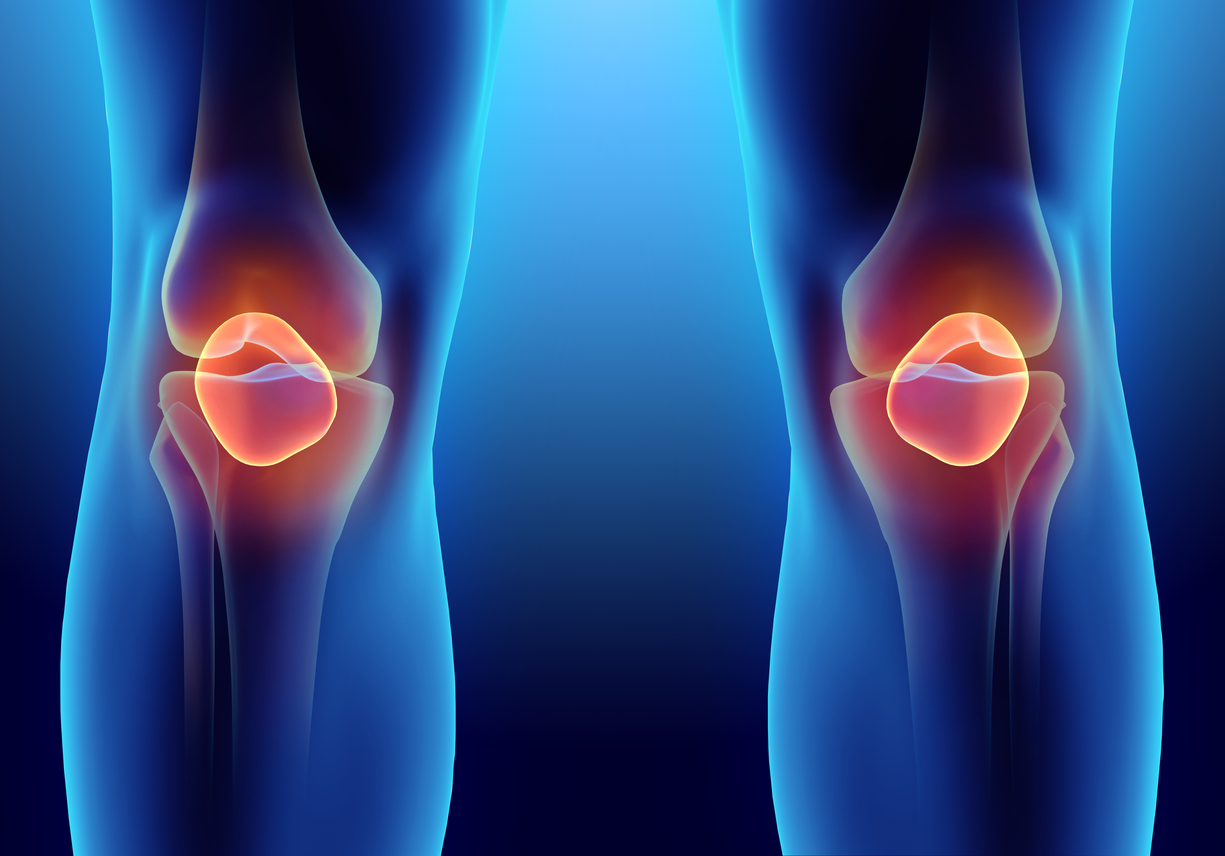

Mi az a térdkalács?

A térdkalács is részt vesz a térdízület felépítésében. A négyfejű combfeszítő izom ínjába ún. szezám csontként (az inakba integrált csontok) van beágyazva. Az ín és maga az ízület mechanikus védőeszköze, nyújtáskor és hajlításkor a térdkalácsárokban felfelé és lefelé mozog. Ez általában nem fájdalmas és zajtalan.

Mi a térdkalács szerepe?

A térdkalács segíti az izmokat, miközben hajlítják és kiegyenesítik a lábat. Gyakorlatilag térdkalács nélkül a térd hajlítása és kinyújtása sokkal nagyobb energiát igényelne a combizmainktól, miközben a térdben lévő inak is sokkal gyorsabban kopnának. Funkciója a fizikából vett hasonlattal élve gyakorlatilag egy csiga. A térdkalács eközben a térdízületet is védi.